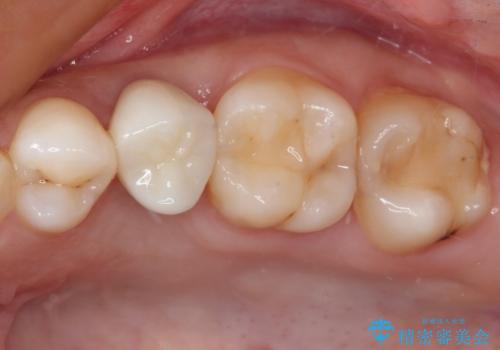

抜歯と言われた奥歯 根管治療と補綴治療